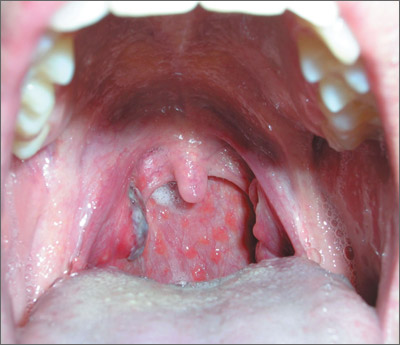

Mucocutaneous ulceration in a previously healthy man

A 36-year-old Caucasian man sought care at our facility for rapidly progressive painful ulcers that were affecting his throat, tongue, genital area, and other parts of his body. He said that the lesions erupted 6 days earlier, and indicated that he had a history of recurrent oral aphthous ulcers.

Physical examination revealed 2 large inflammatory necrotic ulcers on his palate and right tonsil, with multiple small ulcers on the border of his tongue (FIGURE 1). Skin examination revealed scattered crateriform ulcerated plaques—particularly over his forearms, back, and scalp (FIGURE 2). Genital examination revealed a large necrotic ulcer underneath his glans penis, with several satellite perigenital ulcers in the groin. Examination of the antecubital fossa revealed pathergy from a blood test and intravenous cannula (FIGURE 3). There was no ocular involvement.

We diagnosed Behçet’s disease (BD) in this patient based on his clinical presentation.

BD was first described by Hulushi Behçet in 1937 as a triad of oral ulcers, genital ulcers, and uveitis.1 BD is a rare multisystem inflammatory disorder of unknown cause and is prevalent along the Silk Road, an ancient trade route from the Far East to the Mediterranean.

The development of ulceration at the site of superficial skin injury is typical of BD and is termed pathergy. Before he was referred to us, he had had multiple venipunctures while being investigated for a presumed infective illness.